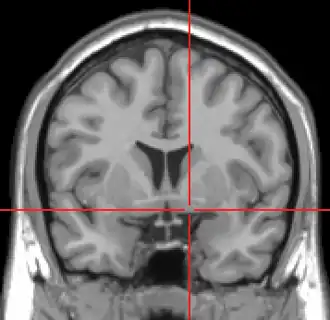

MRI showing a coronal plane of the head with marks showing the location of the substantia innominata, the region in which the nucleus basalis is found.

The nucleus basalis in humans is a somewhat diffuse collection of large cholinergic neurons in the basal forebrain.[2] The main body of the nucleus basalis lies inferior to the anterior commissure and the globus pallidus, and lateral to the anterior hypothalamus in an area known as the substantia innominata.[1] Rostrally, the nucleus basalis is continuous with the cholinergic neurons of the nucleus of the diagonal band of Broca.[1] The nucleus basalis is thought to consist of several subdivisions based on the location of the cells and their projections to other brain regions.[2] Occasional neurons belonging to the nucleus basalis can be found in nearby locations such as the internal laminae of the globus pallidus and the genu of the internal capsule.[1]